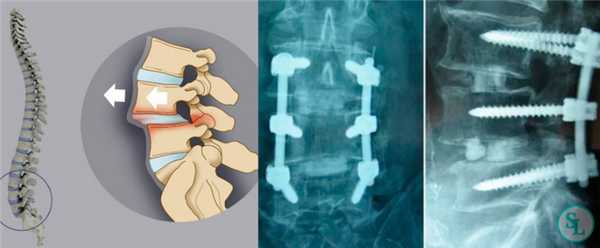

Операция стабилизации позвоночника: описание, показания, статистика и цены

Стабилизацией называется хирургическая установка специальных приспособлений на позвоночник, которые фиксируют части позвонка или смежные ниже- и вышележащие тела, препятствуя их смещению по отношению друг к другу и ликвидируя деформирование хребтовой оси. Проще говоря, стабилизирующая операция предполагает коррекцию положения, предотвращение нестабильности и повышение опороспособности позвоночного столба на любом из его сегментарных уровней. Процедура сложная, длится от 2,5 до 4 часов, выполняется под общим наркозом.

В большинстве случаев проблемный сегмент стабилизируют с помощью металлоконструкций, чаще представленных транспедикулярными системами и пластинами с винтами из высокотехнологичных сплавов металла. В хирургии такая техника называется инструментацией позвоночника. Кроме металлоконструкций, для стабилизации также могут быть применены полимерные устройства, сделанные, например, из углеводородного волокна или резорбирующегося высокомолекулярного биополимера. К отдельной разновидности стабилизирующих вмешательств, которые не причисляют к инструментации, относят установку кейджей имплантатов межпозвоночных дисков.

В преобладающем количестве подобные операции заключаются в достижении полного обездвиживания патологических уровней за счет прочного скрепления двух или более позвонков ригидными конструкциями. Это позволяет позвонкам с течением некоторого времени (от 3 до 6 месяцев) срастись между собой и образовать единый неподвижный костный блок. То есть, на прооперированном поле подвижность между позвонками будет заблокирована, а человек сможет нормально двигаться и ходить, не испытывая при этом боли и прочих неврологических расстройств.

Системы стабилизации позвоночника жесткого типа

Жесткие, или неподвижные металлоконструкции подразумевают закрепление позвонков в постоянном фиксированном положении. Устанавливаются они из заднего доступа (со стороны спины) под контролем КТ и рентген-аппаратуры. Крепятся к позвонкам резьбовыми винтами, которые погружают в костные тела на глубину до 80%. Рекомендуют ставить подобного плана системы сугубо в безальтернативных случаях, если ни один другой вид лечения не сможет решить проблему с поврежденным отделом позвоночника.

Стабилизация поясничного отдела.